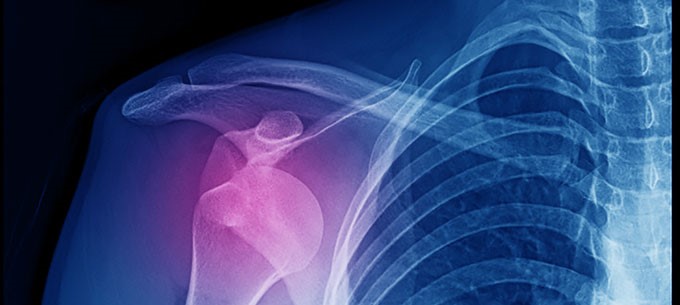

A traumatic shoulder dislocation occurs when the head of your upper arm bone (humerus) pops out of your shoulder joint due to the force of a trauma. The shoulder joint is especially prone to dislocation as it is a ball and socket joint with a very shallow socket. This allows for greater movement but also increases the risk of dislocation.

In either case, the shoulder joint is damaged, normally injuring the bumper around the shoulder joint (labrum) and sometimes the bone of the joint socket as well, along with creating a ‘dent’ in the head of the humerus. This damage makes it more likely that the shoulder will dislocate in the future — this is known as traumatic shoulder instability.

It is important to get your humerus back into your shoulder joint as soon as possible, so you should go to A&E where a doctor can treat your dislocated shoulder. You may also need an X-ray to check if you have sustained a fracture.